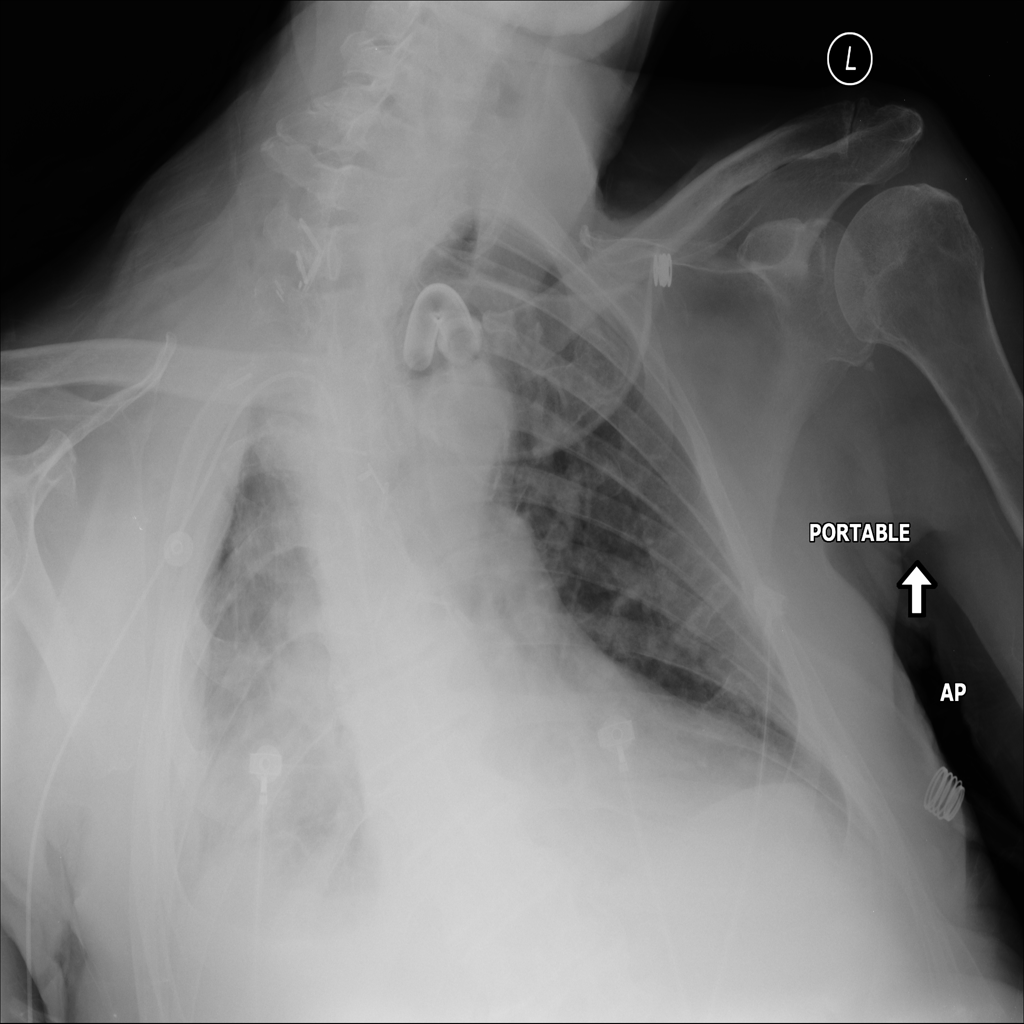

PAT-D7A5 · IMG-000Mass

PAT-D7A5 · IMG-000

PA